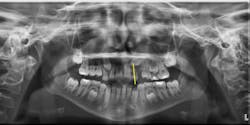

Evaluate the positions of the unerupted canines on a panoramic radiograph for all patients at ages eight and nine. Whenever the crown of the canine crosses the long axis of the lateral incisor, as shown in Figure 1, the canine may become impacted.